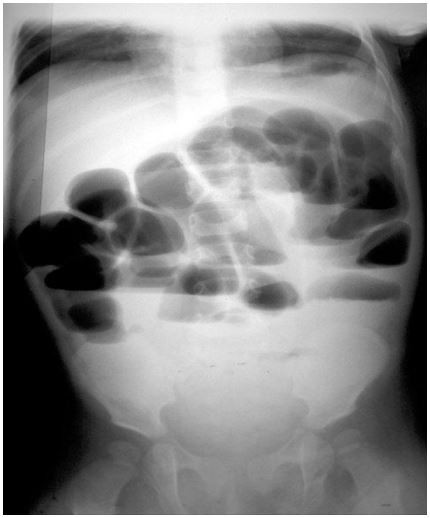

Menino, 4a, sem queixas anteriores, é atendido no pronto socorro, afebril, com dor abdominal intensa, tipo cólica, acompanhada de vômitos biliosos e parada de eliminação de gases e fezes. Realizou este radiograma de abdome em ortostática. Qual é a hipótese diagnóstica mais provável?